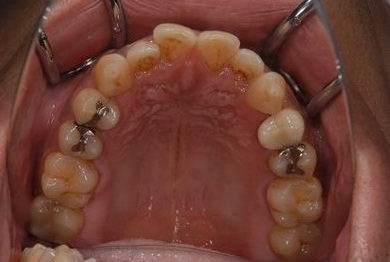

セラミック治療+歯肉歯槽骨整形術

| 性別/年齢 | 男性 / 45歳 | ||||||||||||||||||||||||||||||||

| 主訴 | 詰め物をしている歯が割れてしまったので、治療して欲しい。 | ||||||||||||||||||||||||||||||||

| 治療方針 | セラミック治療にて、審美的回復を行う。 | ||||||||||||||||||||||||||||||||

| 治療内容 | メタルボンドセラミッククラウン1本(メタルボンドセラミック用土台1本)、歯肉歯槽骨整形手術 | ||||||||||||||||||||||||||||||||

| 総治療費 | 157,185円 | ||||||||||||||||||||||||||||||||

| 治療期間 | 7ヶ月 |